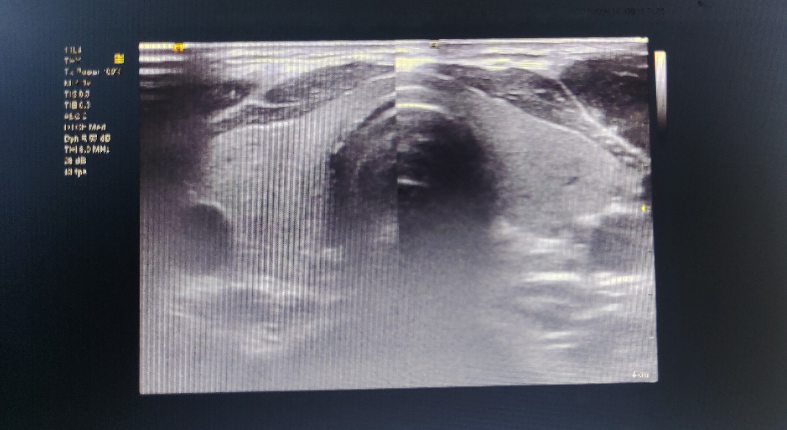

二、再明白:甲状腺彩超究竟查什么?

甲状腺彩超是一项无创伤、无辐射的检查,通过彩色多普勒超声,它主要完成以下“任务”:

1. 观察甲状腺的形态与大小,判断是否存在肿大或萎缩。

2. 查看甲状腺内部的结构与回声,识别是否有结节、囊肿或炎症改变。

3. 评估甲状腺的血流分布,辅助判断功能状态。

这项检查常用于排查结节性甲状腺肿、甲状腺肿瘤、甲状腺炎、甲状腺功能亢进(甲亢)等疾病,同时也是甲状腺疾病治疗后效果评估的重要手段。